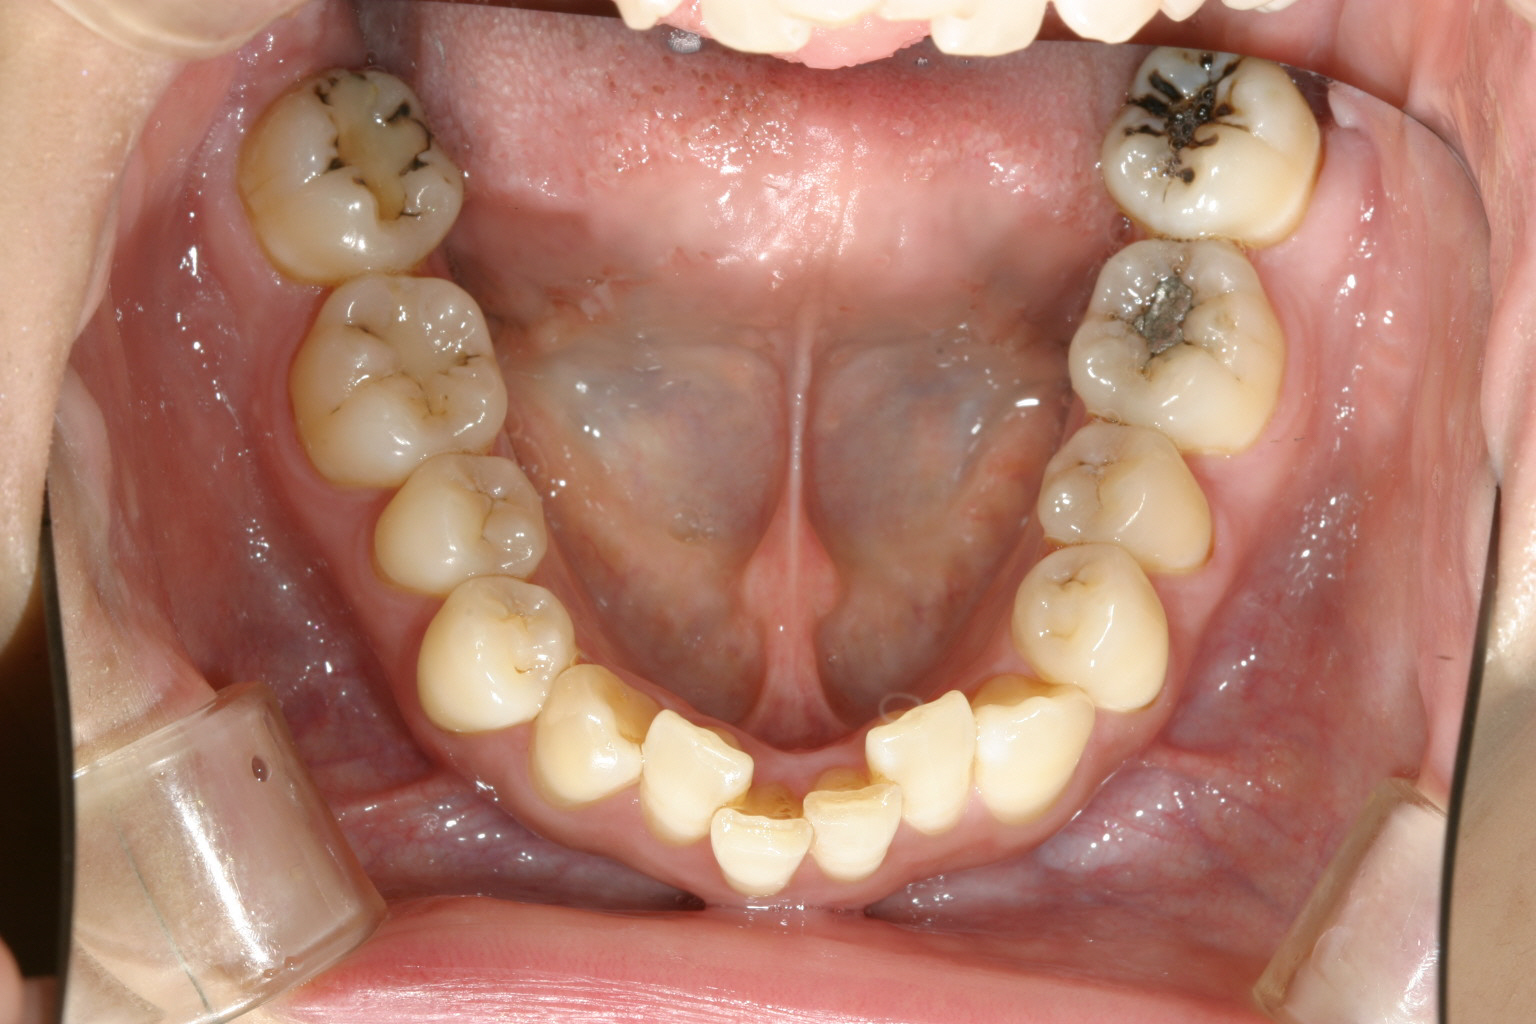

犬歯が飛び出しアーチは崩れ凄いことになっています。

下顎は少しアーチが狭く少し叢生が目立ちます。

上顎左右小臼歯抜歯して治療致しました。

下顎は非抜歯で叢生改善してます。